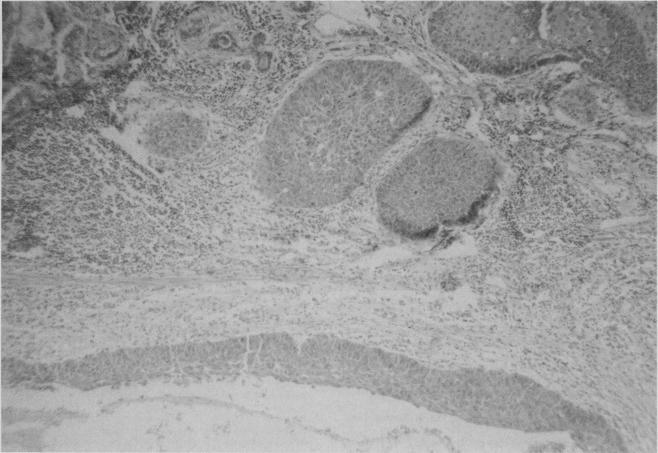

A pilot screening program for the early detection of lung cancer was carried out in Saskatchewan in 1968 using chest roentgenography and cytologic examination of sputum samples. The yield from 23 000 men aged 40 years and over was only 10 cases. Nine of the men had advanced disease. One had occult lung cancer. A period of 31 months elapsed between the discovery of malignant cells in this patient's sputum and roentgenographic localization of the tumour. Following pneumonectomy he has survived with no discernible residual or metastatic tumour for 12 years. The morphologic changes in the resected lung provided a basis for discussing the preclinical phase of squamous cancer of the lung, the treatment of occult cancer and multicentric primary pulmonary tumours. The survey would have been more successful with a narrower target group and more frequent examination.

1968年在萨斯喀彻温省开展了一项肺癌早期检测的试点筛查项目,采用胸部X线摄影和痰标本细胞学检查。对23000名40岁及以上男性的筛查结果仅发现10例病例。其中9名男性患有晚期疾病。1名患有隐匿性肺癌。该患者痰中发现恶性细胞与肿瘤的X线定位之间间隔了31个月。肺切除术后,他已存活12年,未发现明显的残留或转移性肿瘤。切除肺的形态学变化为讨论肺鳞状细胞癌的临床前期、隐匿性癌的治疗以及多中心原发性肺肿瘤提供了依据。如果目标群体更窄且检查更频繁,该调查可能会更成功。